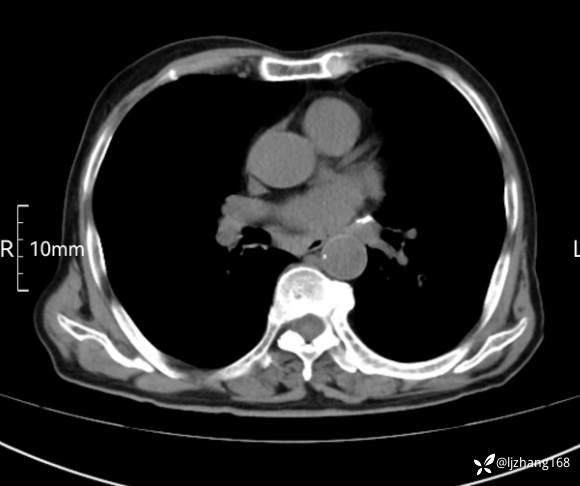

辅助检查:胸部CT:双肺肺气肿,间质性病变,血气分析:PH 7.413, PCO2 29.2mmHg, PO2,81.8mmHg,乳酸 3.3mmol/1,剩余碱-4.0mmol/1,HC03 18.8mmol/1。全血超敏C反应蛋白:超敏C反应蛋白 135.60 mg/L、 白细胞 14x19^9/L,中性粒细胞11.6x10^9/L。